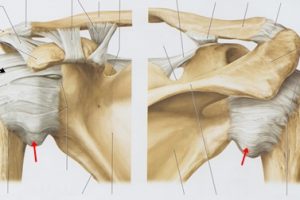

実はこの小胸筋という筋肉は体の前側にあるのですが、肩甲骨の上の方「烏口突起(うこうとっき)」という場所についていて、筋肉が縮こまると肩甲骨を前側に傾かせてしまいます。

肩甲骨が前に傾くと、肩が本来のポジションでなくなってしまうので、きちんとバンザイの動作ができなくなってしまいます。

この状態で運動を続けていくとどんどん痛みが出やすい体になるのと、小胸筋の間を通っている神経や血管を圧迫してしまいます。